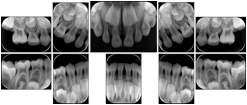

OO.1.3 Cardiology

Cardiac stress testing acquires images in at least two patient states, rest and stress, and typically with several different views of the heart to highlight function of different cardiac anatomic regions. Image review typically involves simultaneous display of the same anatomy at two patient states, or multiple anatomic views at one patient state, or even simultaneous display of multiple anatomic views at multiple states. This applies to all cardiac imaging modalities, including ultrasound, nuclear, and MR. The American College of Cardiology and American Society of Nuclear Medicine have adopted standard display layouts for nuclear cardiology rest-stress studies.

Stress Echocardiography Structured Display

Figure OO-5. Stress Echocardiography Structured Display

Stress-Rest Nuclear Cardiography Structured Display

Figure OO-6. Stress-Rest Nuclear Cardiography Structured Display